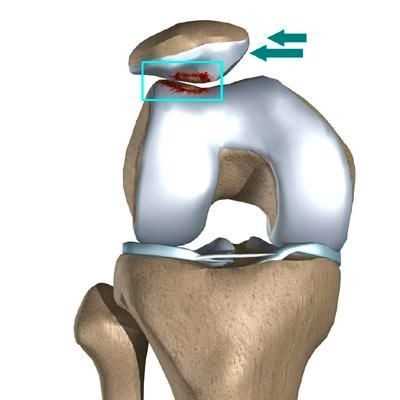

Латеральный вывих надколенника характеризуется разрывом медиального ретинакулюма (медиальной пателло-феморальной связки) коленного сустава. Повторный вывих у пациента — главный признак не выполнения медиальной пателло-феморальной связкой своих функций из-за перерастяжения после первичной травмы.

Вывих надколенника, как первичный, так и повторный, ведет к значимому повреждению хрящевого покрова. Как результат — появляется стойкий болевой синдром и снижение физической активности пациента.